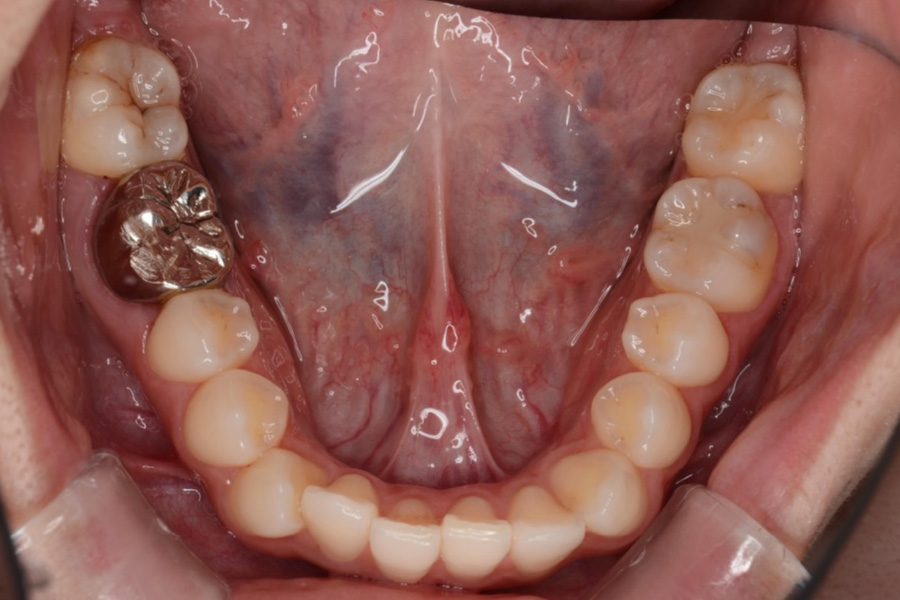

【30代女性】八重歯を

インビザライン矯正で治療したケース

治療前

主訴 八重歯

期間 2年半

費用 220,000円〜660,000円

(デンタルローン 3,100〜6,600円/月)

治療内容 インビザライン矯正

非抜歯